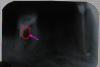

Аленькая Опубликовано 18 октября, 2007 Автор Поделиться Опубликовано 18 октября, 2007 можно спросить - а есть там воспаление в корне или нет? а то врач клятвенно уверял, что корень чистый... но что-то там есть, мне кажется... что-то тёмное вокруг корня... нет? Ссылка на комментарий

Штаматолог Опубликовано 18 октября, 2007 Поделиться Опубликовано 18 октября, 2007 можно спросить - а есть там воспаление в корне или нет? а то врач клятвенно уверял, что корень чистый... но что-то там есть, мне кажется... что-то тёмное вокруг корня... нет? вокруг медиальных есть небольшое а почему импланты не рассматриваете? Ссылка на комментарий

NataLee Опубликовано 19 октября, 2007 Поделиться Опубликовано 19 октября, 2007 А нет ли у уважаемого собрания чувства, что зуб болит, потому там перфо по бифуркации? Или это снимок неудачный? Или мне мерещится? Ссылка на комментарий

Снежана Опубликовано 20 октября, 2007 Поделиться Опубликовано 20 октября, 2007 А нет ли у уважаемого собрания чувства, что зуб болит, потому там перфо по бифуркации? Или это снимок неудачный? Или мне мерещится? Мне тоже кажется, что там не все спокойно. Снимок некачественный, Аленькая сделайте новый и желательно в 2-х проекциях. Ссылка на комментарий

NataLee Опубликовано 20 октября, 2007 Поделиться Опубликовано 20 октября, 2007 ой-ой-ой, расскажите мне про это "перфо" и "бифуркацию", пожалуйста... применительно к моему несчастному зубику... вопрос-то серьёзный, надо с зубом что-то решать... дабы не наворотили мне ещё чего-нибудь... Вы знаете, я не уверена в своей абсолютной правоте. Но мне кажется, что при обработке дистального корня (это тот самый, где находится широкий канал, который удалось пройти, со слов Вашего доктора) сильно истончили его стенку. А может быть, "проткнули" (что и называется перфорацией). Как раз в том месте, где корни раздваиваются (это место называется "бифуркацией"). Я попробовала на этом снимке обозначить то место, о котором говорю. ЗЫ что-то часто я стала рисовать всякие кружочки и стрелочки... Ссылка на комментарий

Аленькая Опубликовано 20 октября, 2007 Автор Поделиться Опубликовано 20 октября, 2007 (изменено) NataLee, спасибо! я посмотрела сам снимочек, там, дейст-но, хорошо видно, что в том месте, которое Вы обвели, какая-то чернота-пустота... вот я щас сижу и думаю - какие вырисовываются перспективы с этим зубом... только удаление? никакой возможности исправления того, что сделано, нет? Изменено 20 октября, 2007 пользователем Аленькая Ссылка на комментарий